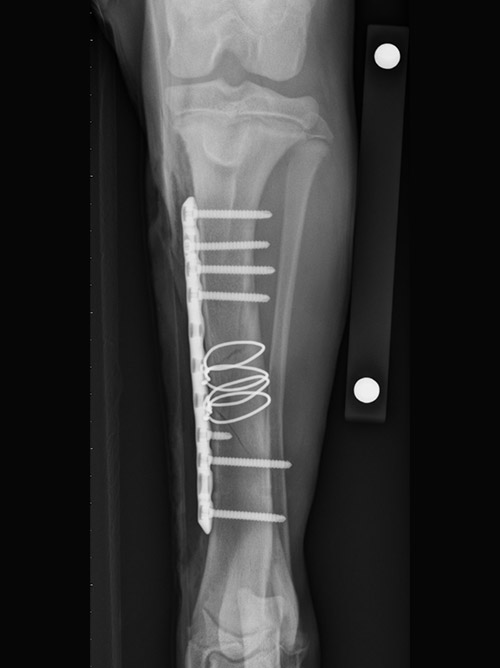

Image 1: Long oblique fracture of the tibia stabilized with two double loop cerclage, and then a medial bone plate